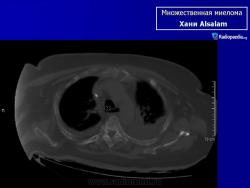

Рентгенологические проявления миеломы бывают классическими с четкими литическими очагами, окруженными ободком склероза, также характерен остеопороз различной степени выраженности, что часто приводит к патологическим переломам. В 25% случаев очаг поражения не выявляется при обычной рентгенографии, при помощи КТ и МРТ выявляют маленькие очаги поражения.

МИЕЛОМА, МНОЖЕСТВЕННАЯ МИЕЛОМА, МИЕЛОМНАЯ БОЛЕЗНЬ, СЕКРЕТИРУЮЩАЯ ЛИМФОМА, ПЛАЗМАЦИТОМА, БОЛЕЗНЬ РУСТИЦКОГО и т.д. – все это синонимы одного заболевания, которое обусловлено неконтролируемым ростом плазматических клеток, продуцируемым костным мозгом. Плазматические клетки, в свою очередь, являются конечной стадией дифференциации В-лимфоцитов – основного звена клеточно-гуморального иммунитета, основная функция которых – продукция иммунных белков – иммуноглобулинов IgG, IgA, IgM, IgE, IgD, участвующих в гуморальном иммунитете. Поэтому в норме костный мозг всегда содержит некоторое количество плазматических клеток. Однако, в случае их неконтролируемого роста увеличение количества плазматических клеток приводит к их сосредоточению в виде плазмацитомы в костном мозге, особенно в позвоночном столбе, тазовых костях, ребрах, плоских костях черепа, головках тазобедренных суставов, в результате чего нормальная костная ткань и костный мозг разрушаются. Очаги деструкции видны при рентгеновском исследовании, но, к сожалению, разрешающая способность рентгена позволяет выявить разрежение костной ткани, если порядка 30% ее уже разрушено. Миеломные клетки продуцируют иммуноглобулин одного вида (моноклональный), который при специфическом электрофоретическом исследовании сыворотки крови и мочи проявляется пиком, называемым М-градиентом, где М - означает моноклональный или миеломный. Отсюда происходит название болезни – миелома. Моноклональные белки (протеины), продуцируемые миеломными клетками, имеют измененную структуру, не выполняют функций иммунитета и называются «парапротеинами». Иногда они теряют какую-то свою часть и могут продуцироваться только моноклональные легкие цепи (белок Бенс-Джонса), или моноклональные тяжелые цепи.